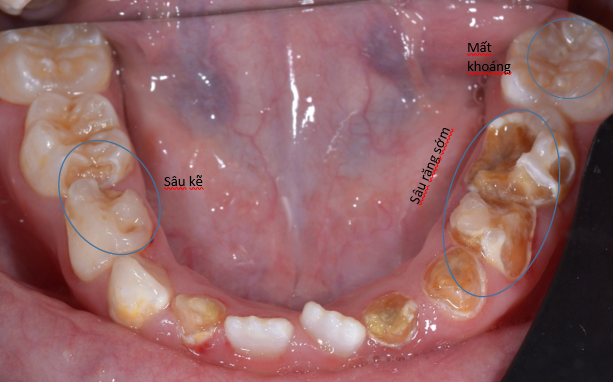

các răng cối sữa bị sâu cần trám lại

Răng sữa có khi bị sâu mặt kế bên hay còn gọi là sâu kẽ răng. Khi răng bị sâu kẽ làm cho các răng còn lại di chuyển vào khoảng trống do sâu răng tạo ra. Điều này làm ngắn chiều dài cung răng. Và khi răng vĩnh viễn mọc lên sẽ bị thiếu chỗ. Việc trám các răng bị sâu mặt bên giúp giữ chiều dài cung hàm tạo điều kiện cho răng vĩnh viễn mọc đúng chỗ.